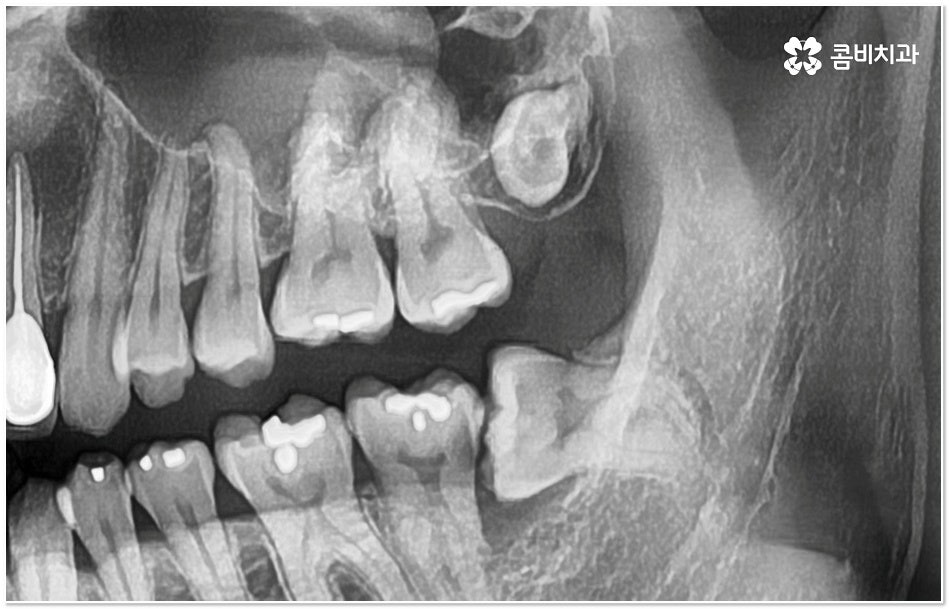

사랑니와 어금니 인접면에 치아 사이 충치 가 발생할 경우 육안으로도 보기 힘들 뿐 아니라 엑스레이를 찍었을 때에도 쉽게 발견하기 힘들 수 있기 때문에 초기에 알아차리지 못하고 치료 시기를 놓치는 경우가 종종 생기며 손상 정도가 많이 심각하거나 위치상 사랑니 발치 후에도 뿌리 끝 염증이 매우 심하거나 치아 사이 충치 로 손상이 심해 치료가 불가능한 케이스의 경우 불가피하게 어금니까지 발치를 해야 할 수 있으므로 이와 같은 상황에 이르지 않도록 평상시에 정기 검진을 꼬박꼬박 받아주는 것이 조기 대처 및 예방 등에 있어 여러 모로 유리하다고 할 수 있습니다.

특히 사랑니가 나오는 시기인 10대 후반부터 20대 초반에 3D CT와 같은 정밀 진단 장비를 통해 사랑니 검진을 한 번 꼼꼼하게 받아보시고 구강 상태를 세세하게 파악한 뒤 비스듬하게 누워있거나 잇몸뼈 속에 매복이 되어 앞 어금니 및 전체 구강 건강에 좋지 않은 영향을 지속적으로 줄 수 있는 상황이라고 판단이 된다면 발치 계획을 세워서 미리 뽑아주는 것도 좋을 거예요.